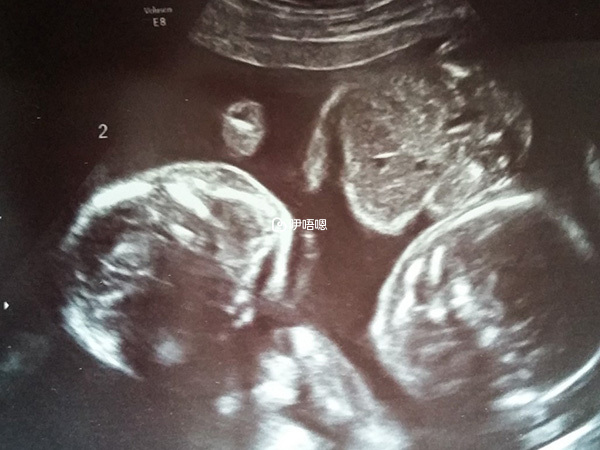

就這樣,膽顫心驚地過了半個月,我的主治醫生第三次決定給我剖腹了。2017年3月9日,在懷孕35周時我見到了我可愛的女兒們。雖然她們生出才4斤多,那麼瘦小,但是評分都是健康的,沒有進保溫箱。